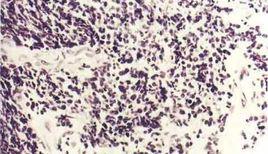

可見到與其它神經內分泌腫瘤相同的結構模式包括巢狀、小梁狀、周圍柵欄狀和玫瑰花結狀生長。也常表現為層狀生長而不伴有上述常見的形態模式。腫瘤細胞常小於三個靜止期小淋巴細胞的大小,具有圓形、卵圓形或梭形核,胞漿稀少,核染色質呈細顆粒狀,核仁缺乏或不明顯,細胞邊界不清,核切跡常見,核分裂數高,平均超過60/2mm2。該腫瘤定義為高級別,因此對其進行分級並不適宜。尚未發現原位性病變。在較大的標本中腫瘤細胞更大,可見散在分布的多形性腫瘤巨細胞,染色質疏鬆,核仁明顯,壞死病變廣泛,細胞凋亡活躍,以及擠壓假象伴血管周圍鹼性DNA殼形成(Azzopardi效應)。

鑑別診斷包括淋巴樣浸潤、其它神經內分泌腫瘤、其它“小圓藍細胞腫瘤”(SRBCT)和原發性或轉移性非小細胞癌。擠壓假象不僅存在於小細胞癌中,也見於類癌瘤、炎症或淋巴瘤的淋巴細胞及分化差的非小細胞癌。在受到擠壓的標本中,觀察到一些保留的腫瘤細胞是診斷SCLC必須的。細胞角蛋白和白細胞一般抗原及神經內分泌標記物和TTF-1的免疫組化染色對診斷有幫助。典型和不典型類癌並不表現小細胞癌中的壞死程度、核分裂及凋亡活性。其它SRBCT包括原發性神經外胚層腫瘤(PNET)的核分裂活性較SCLC低,且表現MIC-2(CD99)陽性,而細胞角蛋白或TTF-1呈陰性。CK20陽性、CK7或TTF-1陰性可以鑑別Merkel細胞癌與SCLC。從形態上區分SCLC和NSCLC是困難的,診斷的基礎是質量好的HE染色切片和固定良好的組織。鑑別不僅僅依靠某一單獨的特徵,而是包括細胞大小、核漿比、核染色質、核仁和核切跡等特徵。相應的細胞學標本可表現保存更完好的腫瘤細胞形態特徵。